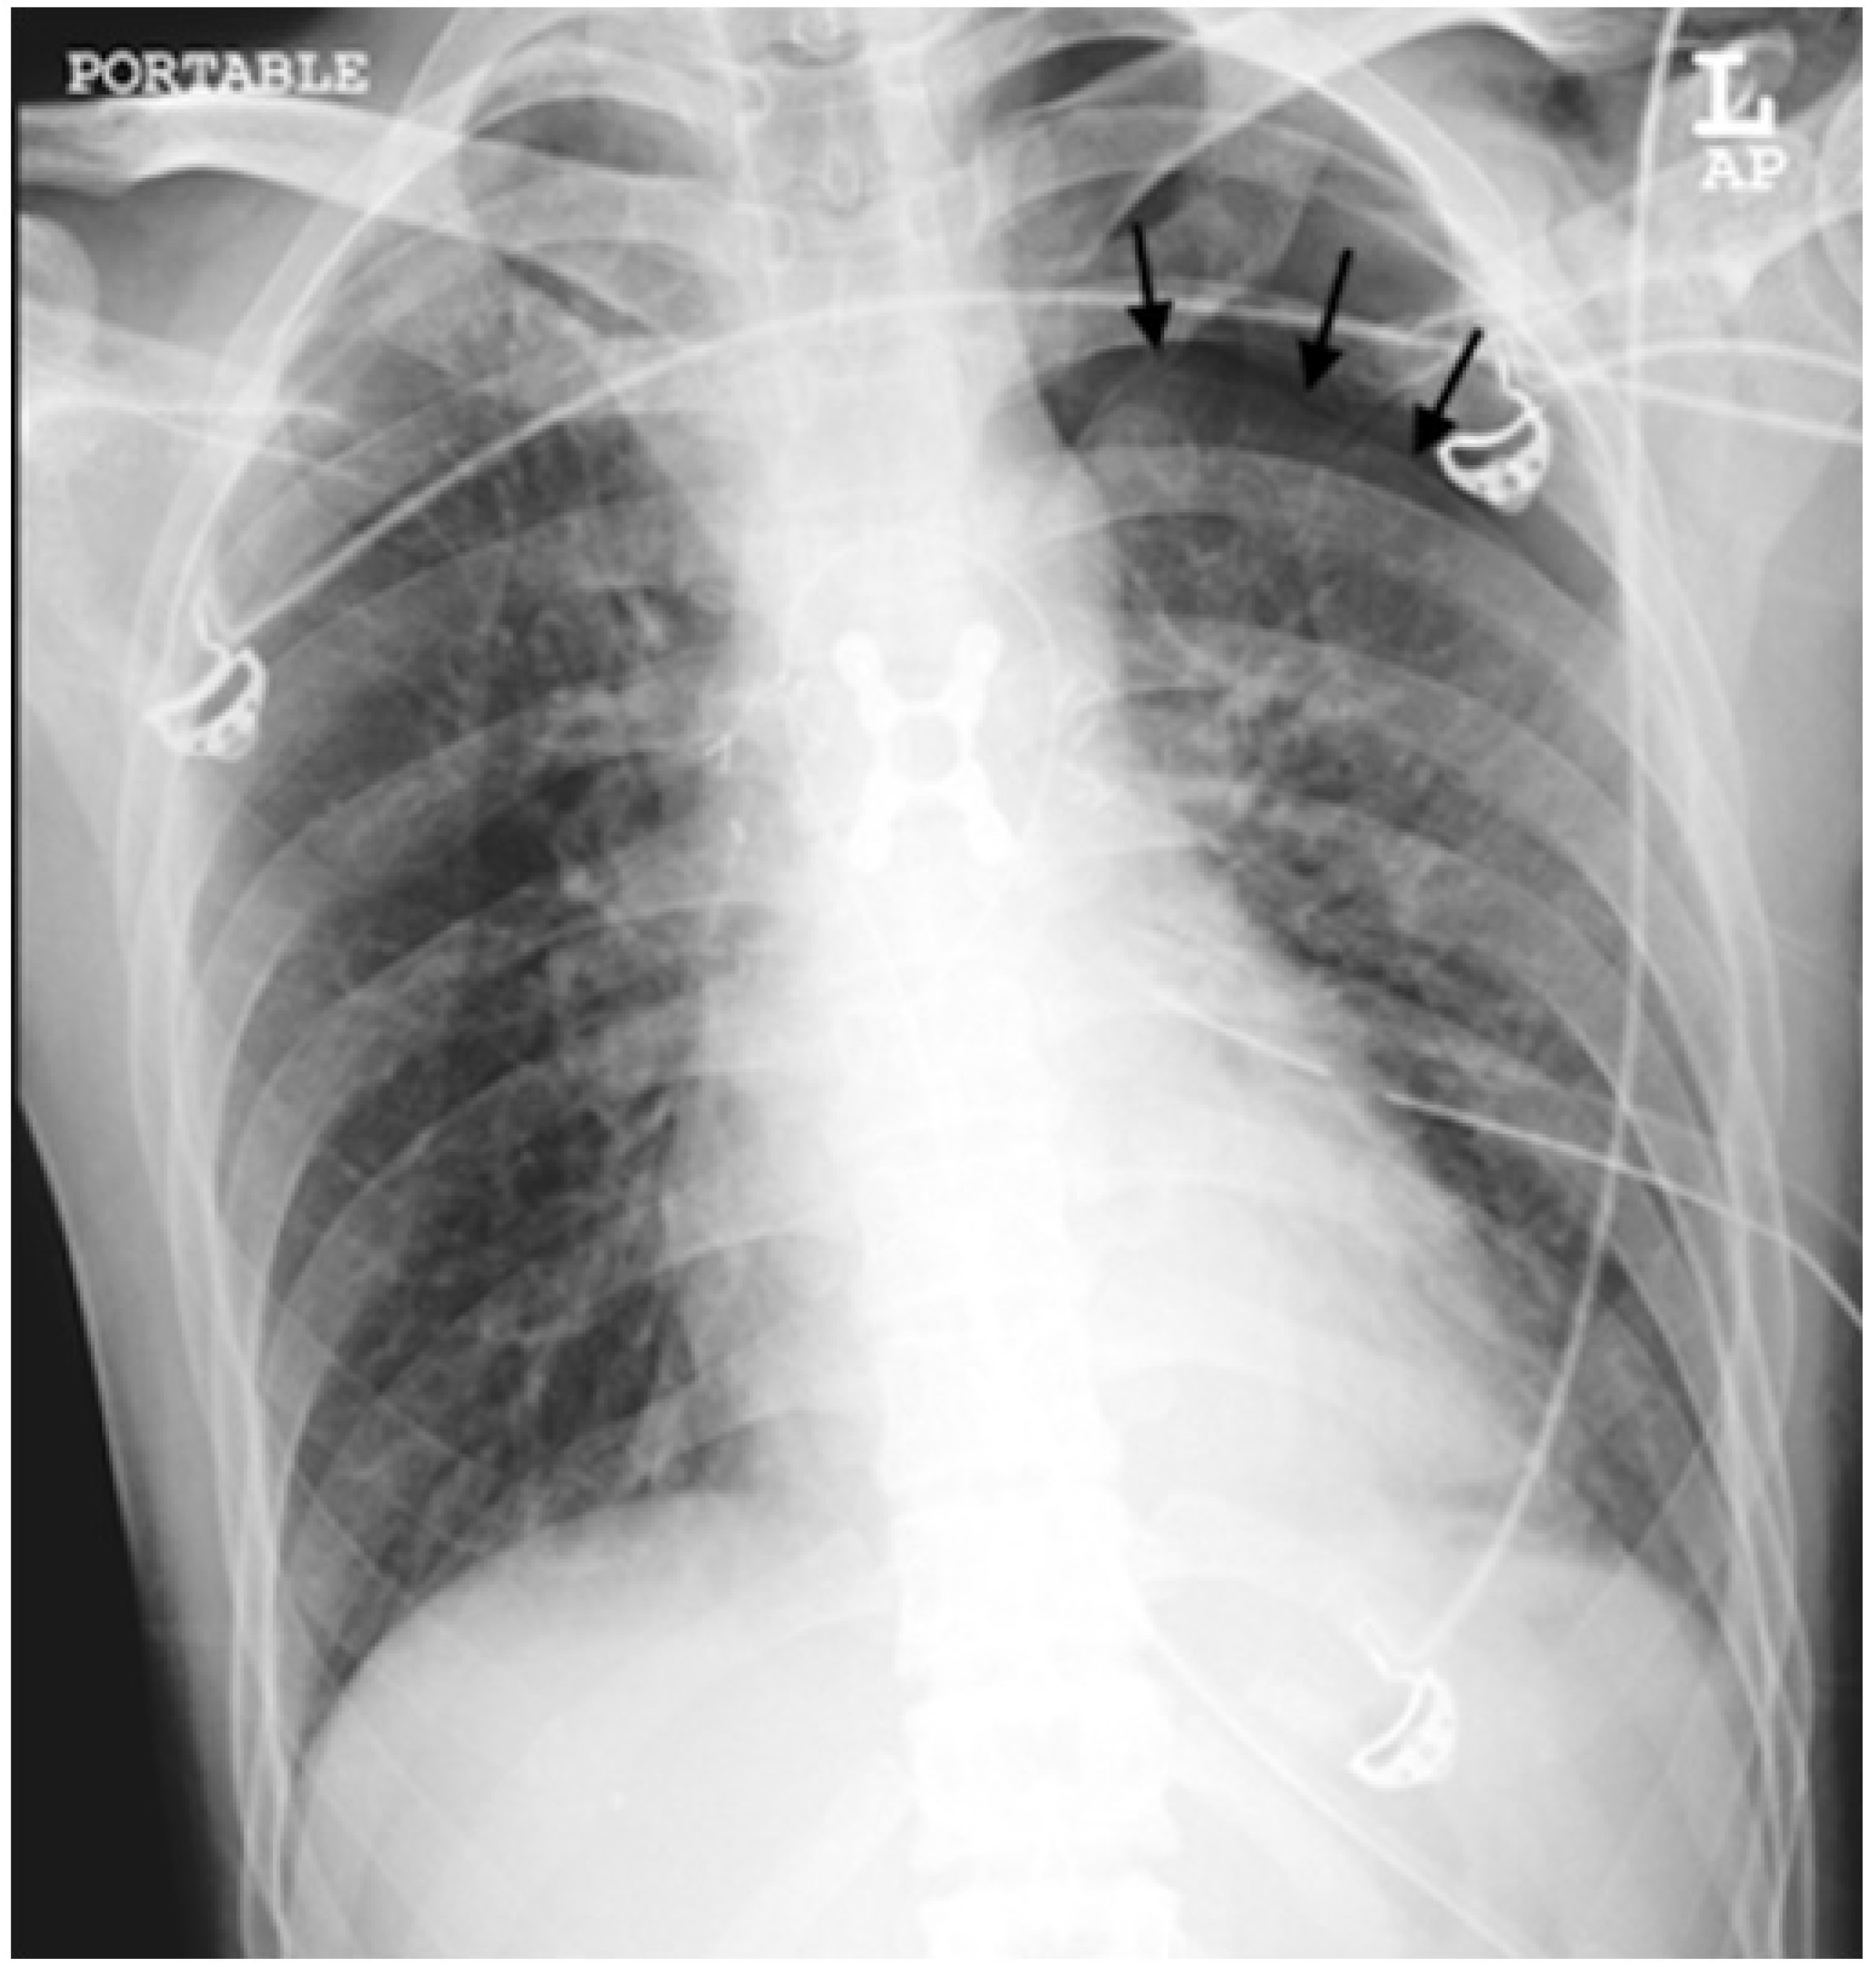

Figure 3. An example of a radiograph categorized as a major discrepancy. A chest radiograph was performed on a 50-year-old man with underlying bronchial asthma who presented with shortness of breath. The trainee missed the pneumothorax in the left hemithorax in about 20% of them (black arrows).